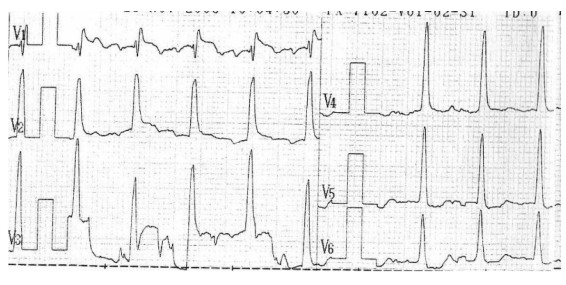

En el postesfuerzo inmediato se comienza a observar elevación del ST en V1 a V3 que alcanza los 2,5 mm, en este momento se administra nitritos sublinguales disminuyendo progresivamente la sintomatología, los cambios electrocardiográficos persisten hasta los 6 minutos del postesfuerzo (figuras 3 y 4).

Figura 3. Postesfuerzo inmediato

Figura 4. Postesfuerzo 3 minutos